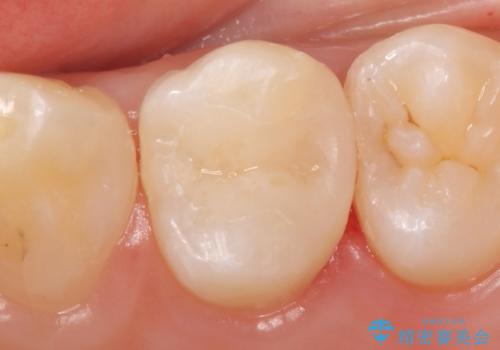

天然歯を模した ハイグレードオールセラミッククラウン